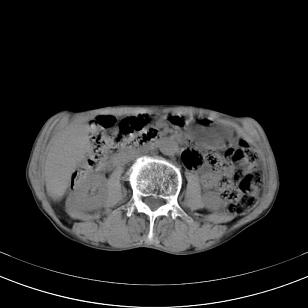

标题: 男,65岁,反复右上腹痛, [打印本页]

标题: 男,65岁,反复右上腹痛,

胃镜提示十二指肠占位